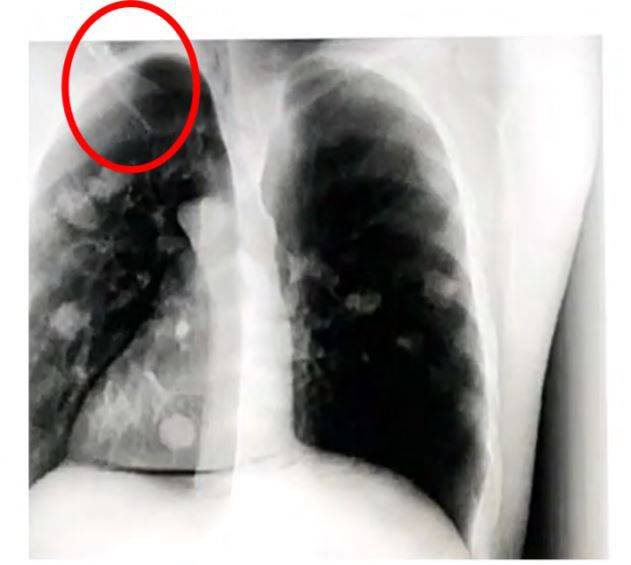

“방사선 전문가들과 굉장히 많은 대화를 나눴다. 나녹스가 정말 기술을 갖고 있다면 나녹스 실제 이미지를 보여줘야 한다고 생각한다. 우리 얘기를 검증하려 나녹스의 업무 제휴 파트너들에게도 접촉했다. 그들은 지난 3월부터 줄곧 이미지를 보내달라고 재촉했다는데, 그러나 누구 한명 받은 적이 없다고 한다. 그리곤 이런 말을 해줬다. ‘우리가 홍보 목적에 쓰이는 것 같다.’ 이는 과거 사례를 봐도 스타트업 주식 홍보를 할 때 종종 쓰이는 수법이다.”

나녹스는 자사 홍보 영상에서 주력 제품인 나녹스아크(Nanox.Arc)로 인간 모형을 촬영하는 장면을 보여준다. 나녹스의 기술이 거짓이 아니라고 주장하는 주된 증거 중 하나다. 그러나 머디워터스 측은 이 시연 영상에서 등장하는 방사선 사진들이 조작됐을 가능성이 있다고 제기했다.

–시연 영상과 홍보 영상에서 무엇을 의심스럽게 봤나.

“사진이 조작됐을 가능성에 대해서는 보고서에 자세히 썼다. 이 밖에 홍보 영상 중 하나에 GE이미징의 블루멘펠트(Blumenfeld) 박사가 등장하는 것도 눈여겨봤다. 그가 업계에서 매우 저명하고 진중한 사람인 건 모두가 인정한다. 그런데 박사가 홍보 비디오에 등장해 하는 말을 들어보면 회사가 약속하는 것에 대해 명확한 얘기를 하지는 않고 있다.” (블루멘펠트 박사는 홍보 영상에서 본인의 커리어를 설명하고 컴퓨터단층촬영(CT) 기기가 의료 영상기기의 혁명이이었다고 말한다.)